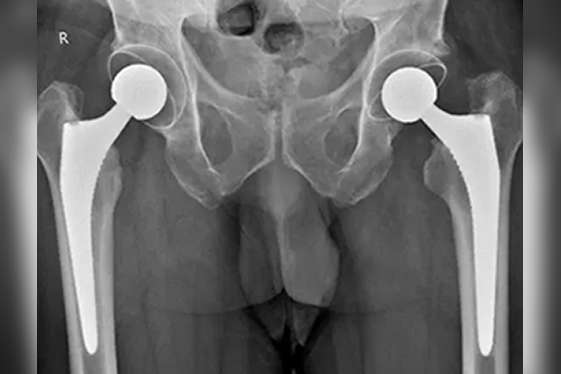

Total Hip Replacement (THR)

Our minimally invasive hip replacement techniques alongwith advanced prosthetic implant materials like ceramic bearings and Vitamin E enriched polyethylene can help provide durable results after surgery. A Total Hip Replacement can help in the treatment of avascular necrosis, osteoarthritis, ankylosing spondylitis, rheumatoid arthritis, inflammatory arthritis, acute hip fracture, and failed treatment of hip fractures. We specialise in Total Hip Replacements for severe deformities, bone defects, fused hips, obese patients, young patients, arthritis with old fractures or previous surgeries, and retained metal implants like rod, plate, and screws. It is possible to live a completely normal life after Total Hip Replacement.